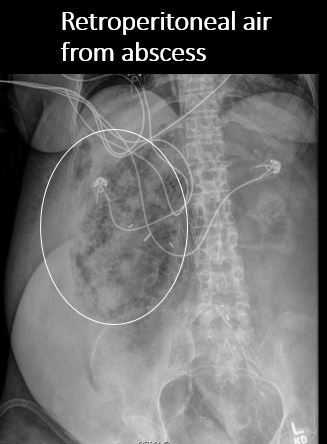

There is air in the retroperitoneum. |

No | NA |